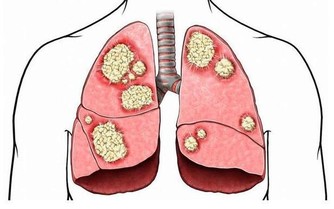

4、骨骼強壯。

中醫認為,腎主骨,骨靠腎精滋養,腎好骨才好。腎氣衰敗會出現骨質疏鬆、腰酸背痛,甚至牙齒出現鬆動。